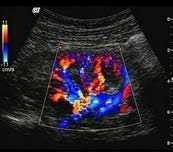

3. PW Power Doppler (Color Power Doppler/CPD)

Power Doppler: Displays amplitude of Doppler signal rather than frequency shift.

Based on amplitude/strength of blood cell motion, not velocity or direction

Image is superimposed over 2D B-mode

Does NOT provide directional information

Highly sensitive to slow flow states

Less dependent on angle of insonation than color Doppler

An ultrasound demonstrating color Doppler application with mixed red, blue, and yellow colors indicating complex flow patterns within a blood vessel, with the region of interest marked by a white box.